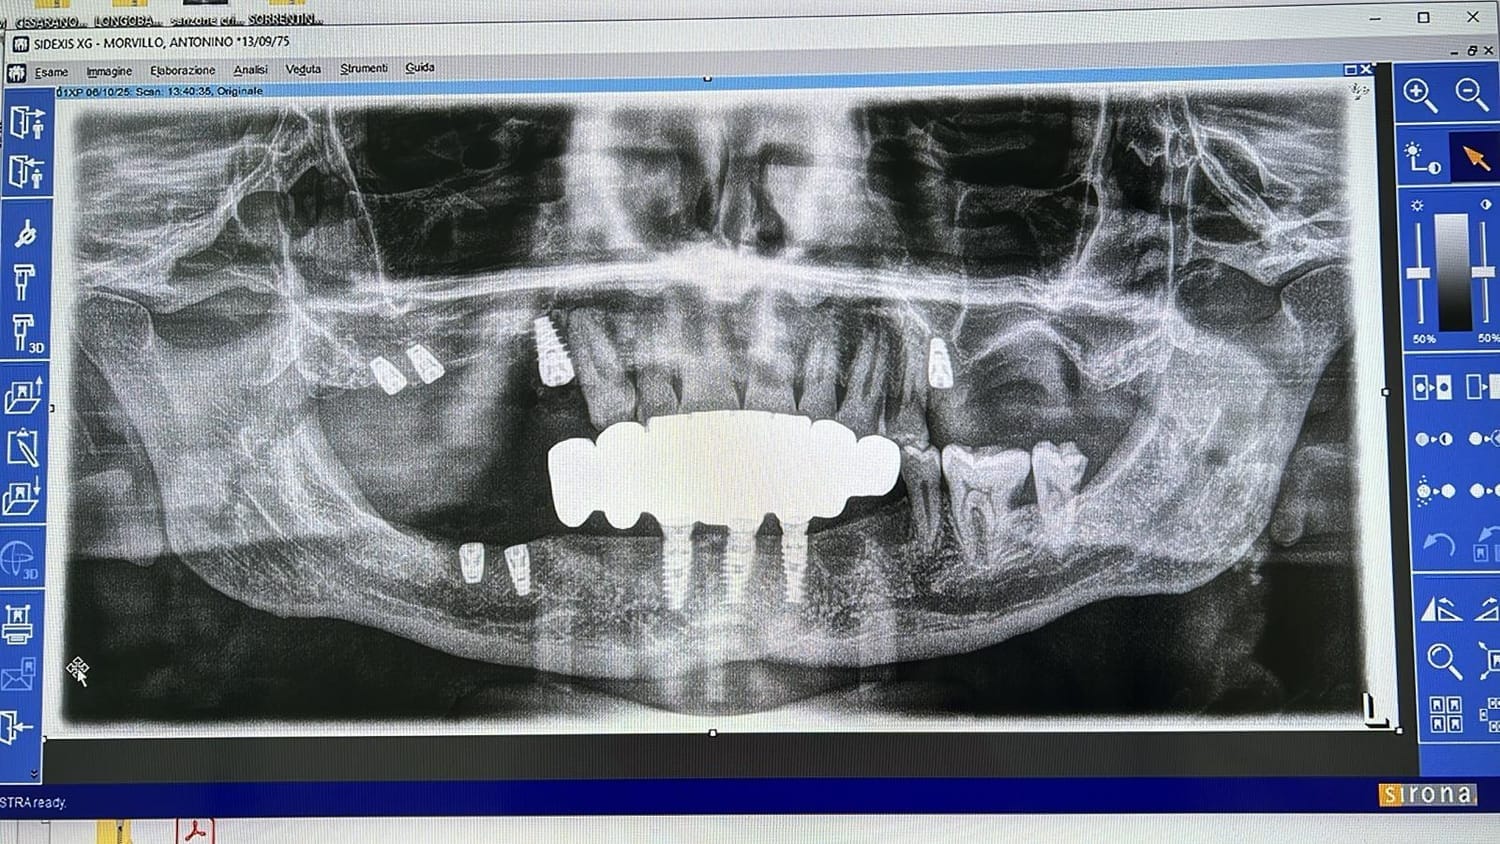

Paziente affetto da atrofia grave con parodontite acuta localizzata.

Caso progettato e realizzato attraverso la tecnica dell'implatologia computer-guidata con impianti short.

Grazie ad una progettazione fatta mediante PC su tac otteniamo preventivamente dove posizionare gli impianti la lunghezza la larghezza e la corretta angolazione di inserimento che ci consente di realizzare le protesi ancora prima di farevlintervento e di evitare tagli e scollamento gengivali che provocano dolore e bruciore riducendo notevolmente itempi di guarigione e i fastidi post intervento